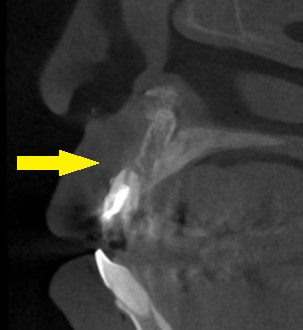

レントゲン写真、CTを撮ってみると、下の写真、中段のように歯根の先まで、骨が吸収されてしまっていました。